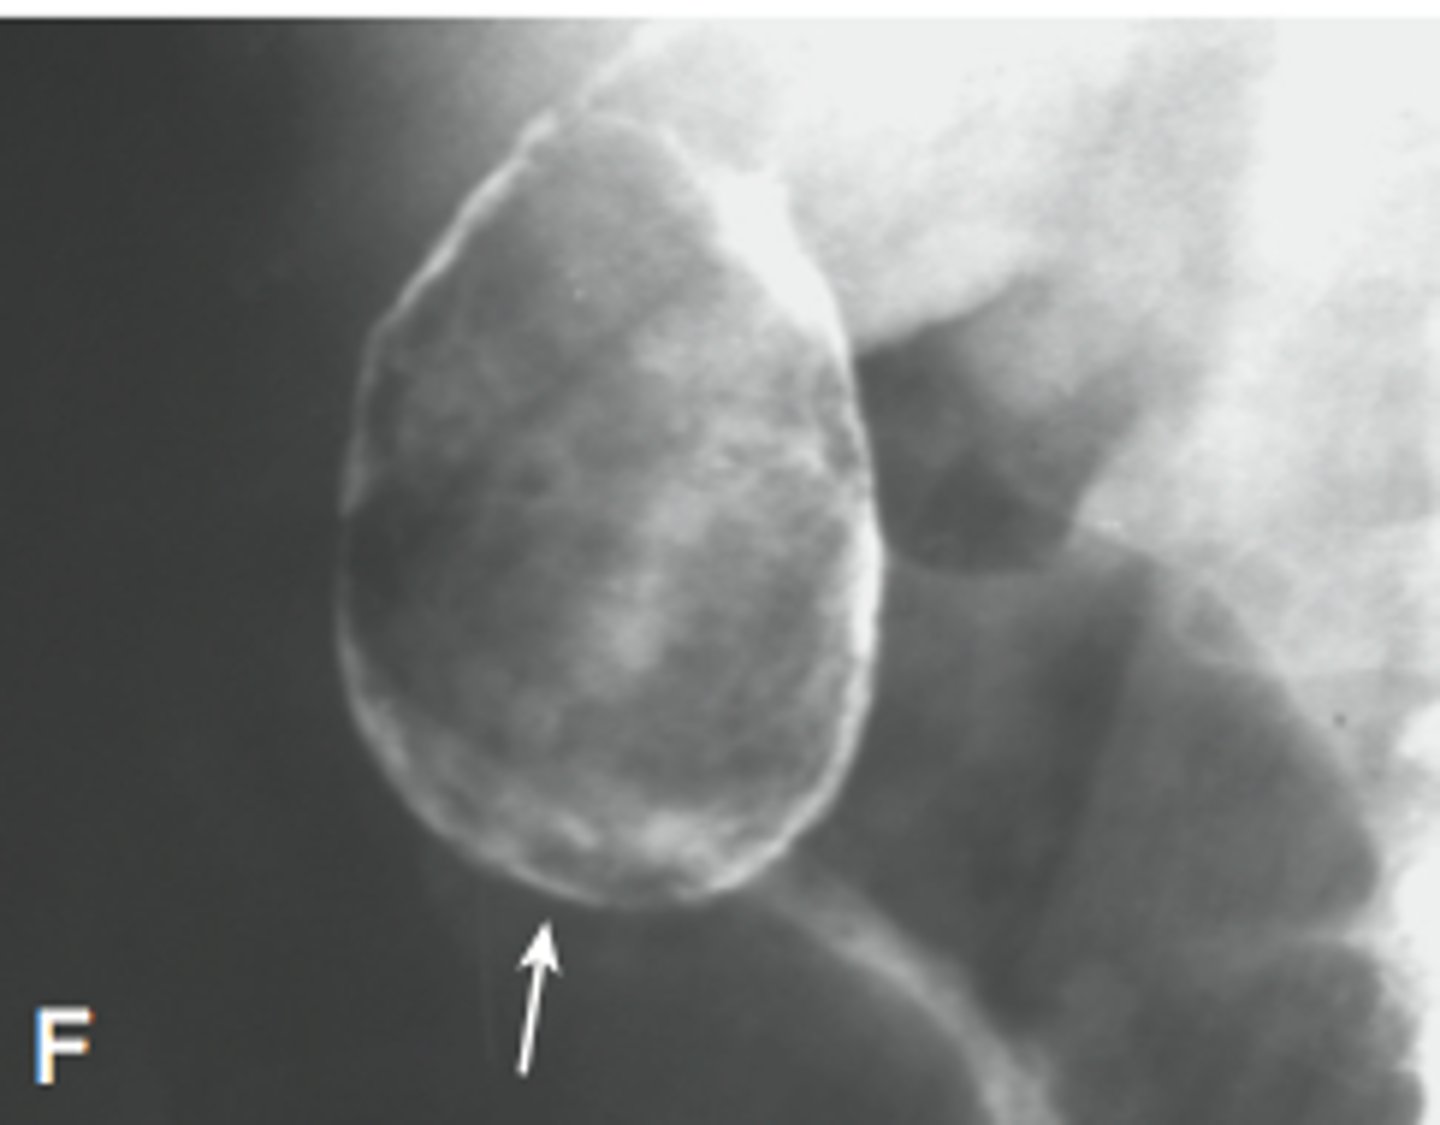

avascular necrosis

bone death due to lack of blood supply, often in proximal and distal femoral head, X-Ray is most used and MRI is most sensitive modality

caused by trauma, long term alcohol use, long term glucocorticoid use, sickle cell anemia, pediatric disorders

findings: devascularized bone becomes denser and more sclerotic